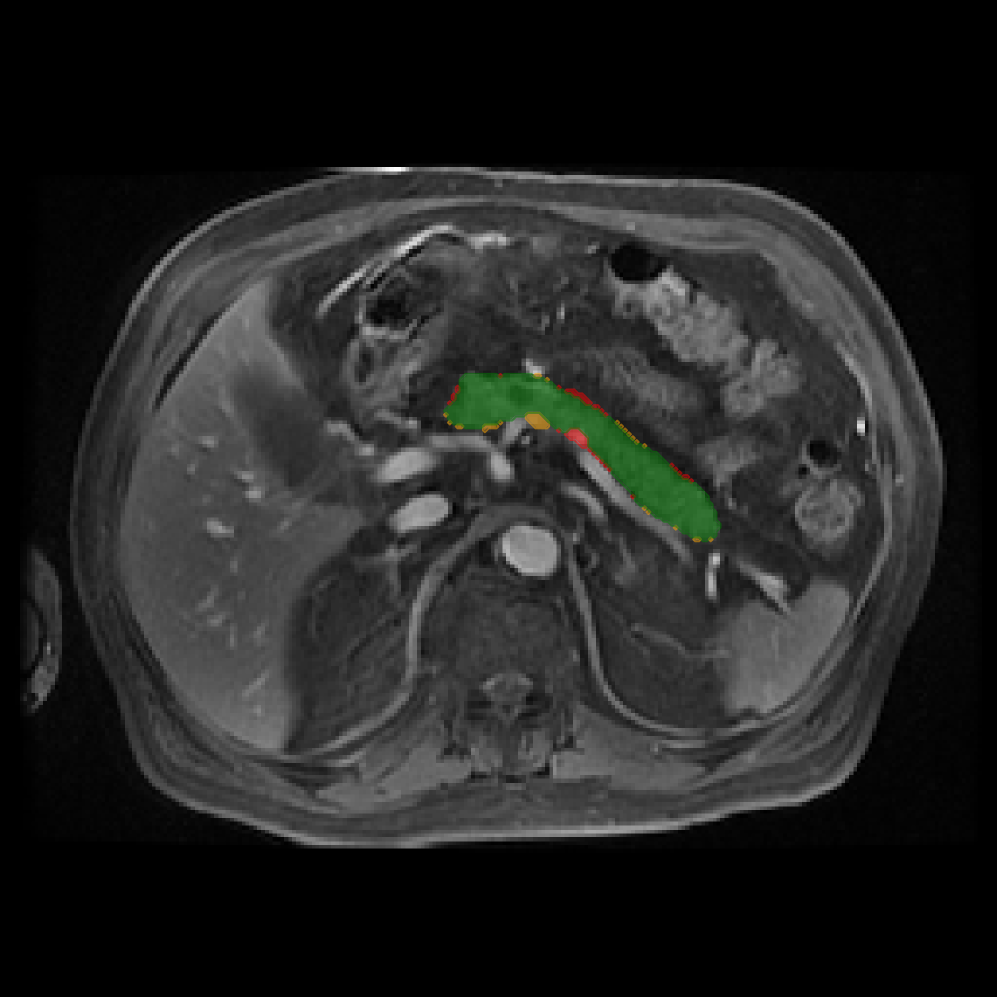

Accurate pancreas segmentation is a critical prerequisite for precise cyst analysis and classification. Recently, we developed PanSegNet [zhang2025large], a novel segmentation architecture incorporating linear self-attention layers [zhang2022dynamic] within the nnUNet framework [isensee2021nnu] to enhance global information modeling capabilities while maintaining computational efficiency (Fig. 1). PanSegNet demonstrated exceptional segmentation performance across both T1W and T2W modalities, achieving mean dice scores of 86.817.30% and 89.626.38%, respectively (Table 1, Fig. 2b-c). This performance significantly exceeded that of Swin-UNETR [hatamizadeh2021swin], one of the most used state-of-the-art transformer-based medical segmentation models, which achieved dice scores of 79.091.40% and 76.290.66% for T1W and T2W, respectively (). In this study, we integrated PanSegNet into our Cyst-X engine along with a classifier for risk prediction. In Section 2.2, we show that the choice of segmentation model affects the classification results. The performance advantage of PanSegNet was consistent across all seven medical centers, demonstrating robust generalization despite variations in imaging protocols and equipment (Table 1). This cross-institutional reliability is particularly important for clinical applications, where model performance must remain consistent regardless of imaging site or acquisition parameters.

2.2.1 Importance of accurate pancreas segmentation in classification

To assess the importance of accurate pancreas segmentation in classification, we evaluated how different ROI sources affect DenseNet-121’s performance. Specifically, we compared classification results using ROIs generated by PanSegNet and Swin-UNETR, both under centralized learning, against a baseline using radiologist-defined ROIs. As shown in Table 2, using PanSegNet’s masks resulted in only a modest performance decline, reflecting its strong segmentation quality. In contrast, Swin-UNETR led to a more substantial drop, demonstrating that inferior segmentation can directly compromise classification. For 3-class classification, the mean AUC dropped from 75.59% (radiologist ROI) to 72.26% with PanSegNet, and further to 66.95% with Swin-UNETR on T1-weighted images. On T2-weighted scans, the AUC declined from 81.09% to 74.18% (PanSegNet) and to 69.63% (Swin-UNETR). A similar trend was observed in 2-class classification: on T1W, AUC dropped from 78.13% to 74.84% (PanSegNet) and 70.20% (Swin-UNETR); on T2W, from 82.37% to 77.01% and 68.92%, respectively. These results emphasize that accurate segmentation—particularly via PanSegNet—is not only essential for volume estimation but also critical to preserving downstream classification performance in the Cyst-X pipeline.